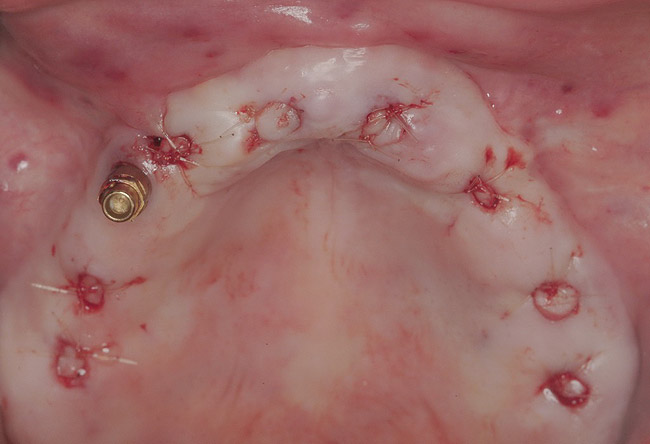

Figure 17  Tension-free primary closure achieved with monofilament PTFE sutures.

Figure 17

Clinical and radiographic evaluation revealed significant alveolar ridge resorption and maxillary sinus pneumatization. The patient was informed that to achieve her goal of wearing a fixed prosthesis, she would require bilateral sinus grafts and anterior ridge augmentation, which she agreed to undergo. Following augmentation of her right and left maxillary sinuses, she presented for reconstruction of her severely atrophic anterior region. Following reflection of a full-thickness flap, severe bone loss was evident, especially in the right canine–lateral incisor region (Figure 15). Following decortication of the buccal cortex with a #2 round bur, a composite graft consisting of 0.8 mg of rhBMP-2/ACS + 0.7 cc of FDBA was adapted to the facial surface of the ridge from the maxillary right to the left canine regions. A bioresorbable PLGA mesh was then contoured and affixed with two PLGA screws 4 mm in length and 1.5 mm in diameter. Additional particulate FDBA graft was then placed under the mesh to obturate the entire space between the bony surface of the ridge and the mesh (Figure 16). A non-cross-linked collagen tape (CollaTape®, Zimmer Dental, www.zimmerdental.com) was applied over the mesh for containment of the particulate bone graft, followed by periosteal-releasing incisions and tension-free primary closure with monofilament polytetrafluoroethylene (PTFE) sutures (Figure 17).

The surgery was initiated with eight mucoplasties using a disposable tissue punch. The autogenous, epithelialized grafts were maintained in aseptic conditions throughout surgery. After gentle irrigation of the implant sites with sterile saline, these eight tissue grafts were re-placed using resorbable sutures to prevent contamination of the implant sites and provide protection from the overlying treatment denture (Figure 22). The transitional denture was relieved, and a resilient reline was performed at the conclusion of surgery. The patient started a 10-day course of amoxicillin 500 mg three times daily, 1 hour prior to surgery, as well as a 6-day tapering dose of methylprednisolone 4 mg the morning of surgery. She was also prescribed an NSAID, etodolac 400 mg to be taken every 8 hours for 3 days, and a chlorhexidine gluconate rinse twice daily. She was advised to only wear the denture when absolutely necessary, and to always remove it before bedtime.